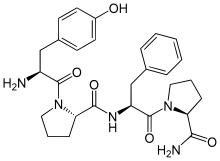

Opioid peptides

Dynorphins

Structures

| Dynorphins | ||||

|---|---|---|---|---|

Big dynorphin Big dynorphin |

Dynorphin A Dynorphin A |

Dynorphin B Dynorphin B | ||

Endomorphins